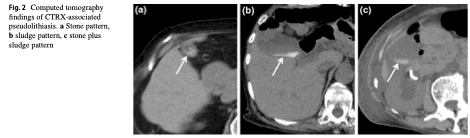

(Jpn J Radiol. 2019 Dec;37(12):826-831.)

・CTRX投与前2ヶ月以内にCT検査がされており, その際は胆石は陰性,

そして投与後に胆石所見を認めた症例で, さらに中止後に胆石所見が消失した症例を抽出

・CT所見は胆泥パターンが11例(64.7%), 胆石が2例(11.8%) , 胆泥+胆石が4例(23.5%)